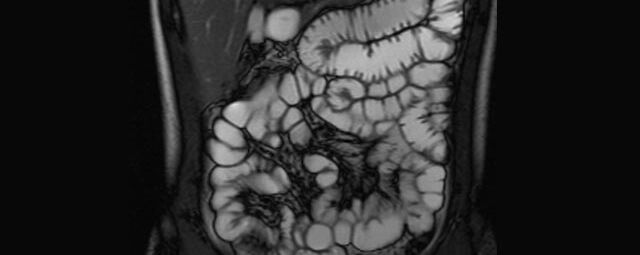

- Dünndarm/Dickdarm

- Chronisch-entzündliche Darmerkrankungen wie Morbus Crohn oder Colitis ulcerosa. Beurteilung der Ausdehnung der Entzündung, Darstellung von Fisteln oder Abszessen bzw. einer Passagebehinderung (MR-Sellink, MR-Kolonographie, beide Untersuchungen nach spezieller Vorbereitung)